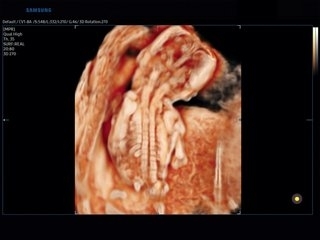

- Realistic Vue — реалистичная 3D-визуализация с виртуальным освещением для родительского консультирования и скрининга;

- Realistic Vue — программа реконструкции реалистичного 3D УЗИ, при котором на объемное изображение накладывается виртуальный источник освещения. Специальный процессинговый алгоритм воспроизводит трехмерную анатомию плода с исключительной детализацией;